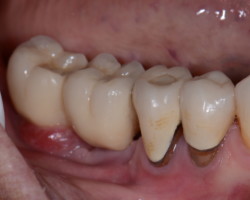

Ciment

Il représente un risque X3,6 de péri-implantite (Dalago 2016), un débordement provoquera systématiquement une mucosite et finira en péri-implantite s’il n’est pas éliminé.

Pour Korch et coll (2014), une « mucosite/péri-implantite sur deux est en rapport avec un excès de ciment.

Source : Korch et Coll